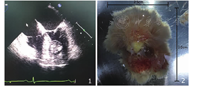

2018年5月在全麻下行左心室占位摘除术。术中经食管超声心动图再次确认左心室占位病变(图1),直视下通过主动脉瓣可见一大小约3.0 cm×2.5 cm占位,质地疏松,边界清,基底部附着于室间隔中间段,带蒂切除占位组织(图2),送检病理科。病理肉眼示:灰黄组织一块,大小约3.0 cm×2.5 cm×1.3 cm,切面灰黄灰红,质软到中。免疫组化结果示:CR(-)、ERG(+)。特殊染色:弹力EVG(+)。病理诊断:(左心室占位)乳头状弹力纤维瘤。患者术后胸痛症状明显改善,复查超声心动图、胸部CT、心电图等均未见明显异常。出院后电话随访半年,患者恢复良好,自诉无胸痛症状复发,复查超声心动图示无肿瘤复发。